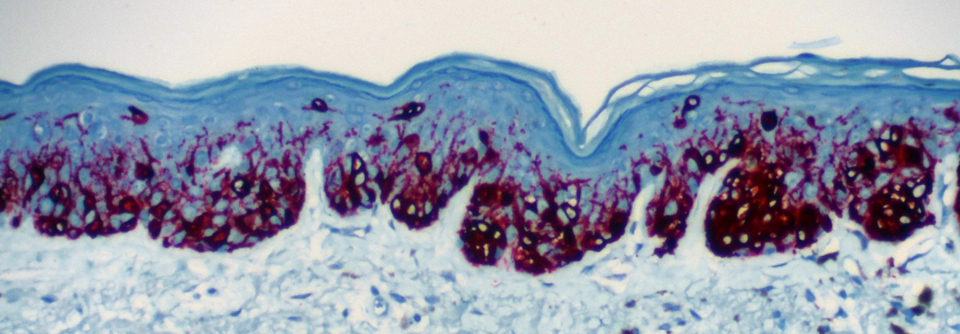

Melanom: Langzeitdaten zeigen Fortschritt durch Immuntherapie

Vor Einführung der Immuntherapie war die Prognose von Patienten mit metastasiertem Melanom sehr schlecht. Das mediane Gesamtüberleben lag unter einem…

mehr

Onkologie und Hämatologie , Dermatologie ASCO 2021